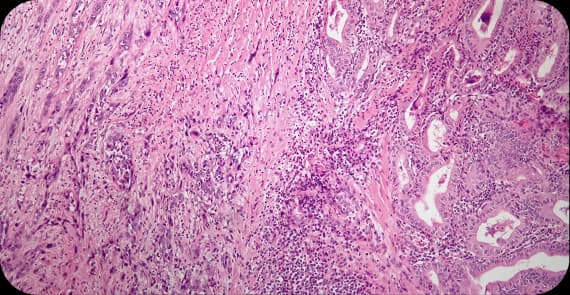

There are several types of thyroid cancer, each with distinct characteristics.

The most common type of thyroid cancer, it is typically slow-growing and often highly treatable.

Typically, it spreads through the bloodstream instead of lymph nodes.

Arises from specialised C cells that produce calcitonin.

This type is a comparatively rare and aggressive form.